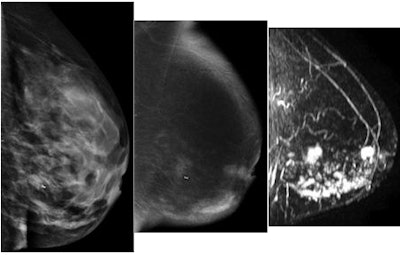

| 39-year-old woman with infiltrating ductal carcinoma and extensive DCIS who presented with left breast pain and nipple retraction. Left mediolateral oblique conventional digital mammography image (left) shows dense breast tissue. Left mediolateral oblique dual-energy contrast mammography (middle) and sagittal subtraction MR (right) images show multicentric disease. Marker clip can be seen on left and middle images. All images courtesy of RSNA. |

Breast MRI and the dual-energy technique both depicted 50 (96%) of 52 index tumors; conventional mammography identified 42 (81%). Of the 52 patients, 47 had invasive ductal carcinoma with or without ductal carcinoma in situ (DCIS), three had infiltrating lobular carcinoma, one had DCIS only, and one had DCIS with microscopic invasion, Jochelson's team wrote.

Lesions found by dual-energy contrast digital mammography ranged from 4 mm to 67 mm. The technique produced two false positives, compared with 13 false positives for MRI.

Breast MR did beat dual-energy mammography in the ability to depict additional sites of malignancy: 16 patients had multifocal or multicentric cancers, and MRI depicted 15 (94%) of these additional sites, while dual-energy contrast mammography found nine (56%). Twenty-five additional ipsilateral lesions were found in these 16 patients: Breast MRI identified 22 of these ipsilateral lesions (88%), dual-energy contrast mammography found 14 (56%), and conventional digital mammography found four (25%).

Dual-energy contrast mammography "had a lower sensitivity for detecting additional ipsilateral cancers than did MR imaging, but the specificity was higher," the authors wrote. "We were able to show that [dual-energy contrast mammography] was comparable to MR imaging for the depiction of the index tumor in patients with known breast cancer."